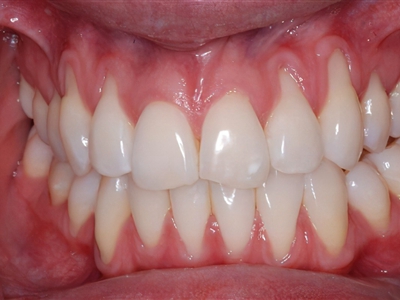

牙龈退缩上排多颗牙的牙根暴露图

牙龈退缩导致上排多颗牙齿的牙龈回缩,部分牙根暴露在外,伴有牙齿松动、口臭等症状,是由于牙周炎、局部受力过大等因素导致。